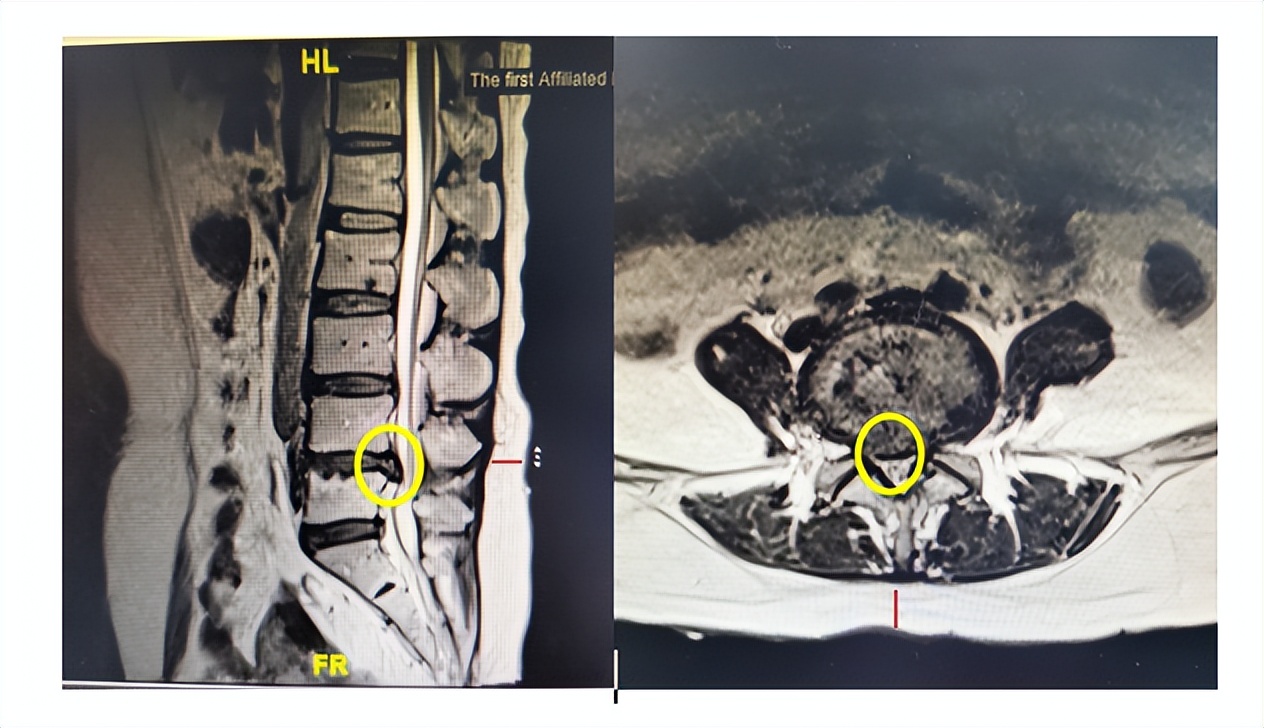

黄圈标记为脱出的间盘组织压迫神经